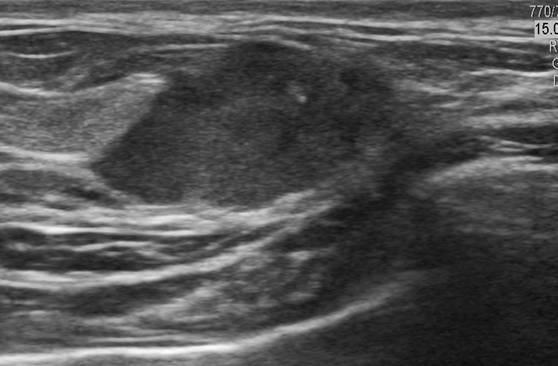

Ung thư vú

» Thông tin: Nữ giới – 33 tuổi.

» Lâm sàng: Khối tuyến vú.